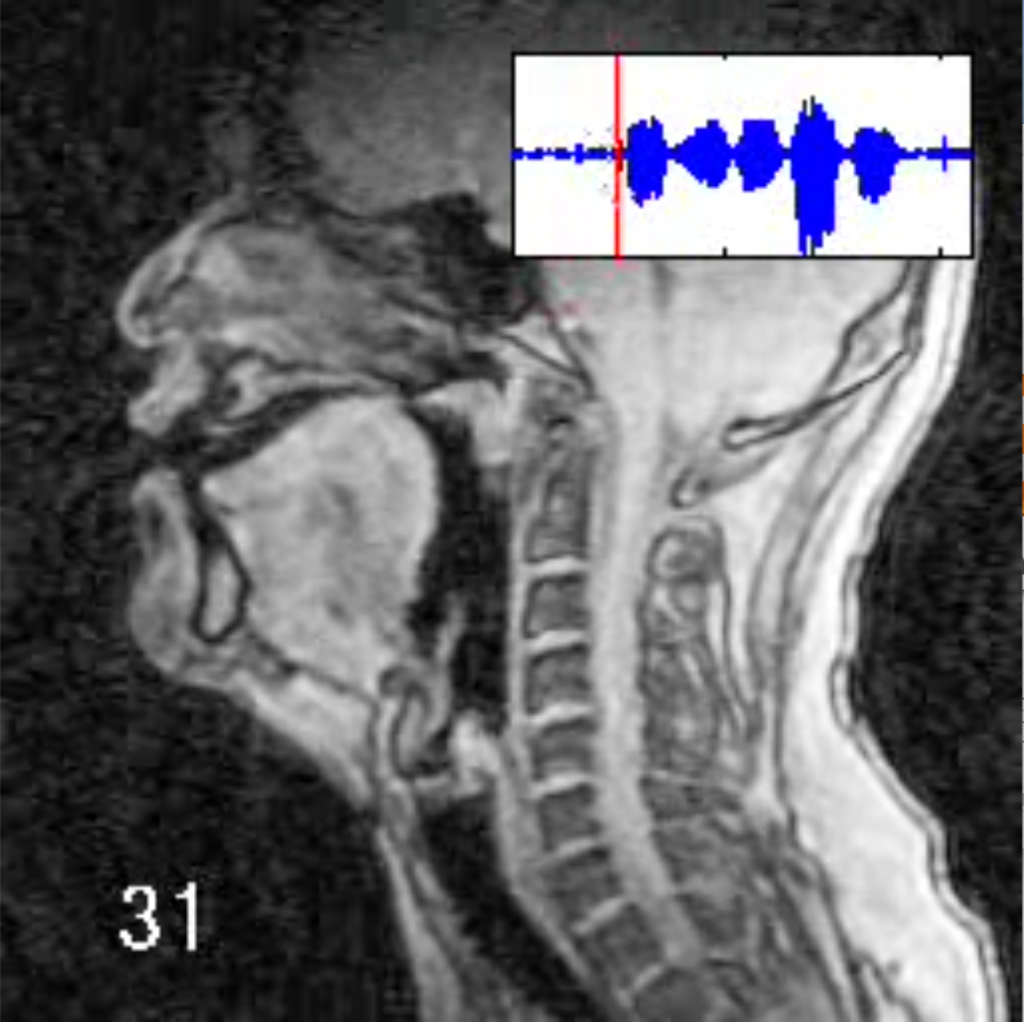

じゃあ次に「たちつてと」と比べてみようか。自分で「か」「た」「か」「た」「か」「た」って発音してみよう。

川原 「か」は舌の後ろ側が動くんだったね。じゃあ、「がぎぐげご」はどうだろう? MRIを見てみようか。「かきくけこ」とほとんど一緒だね。じゃあ「か」と「が」は何が違うのっていう話になる。